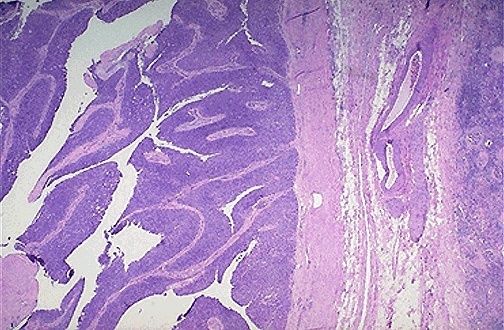

| Carcinoma urotelial microscópico de bajo aumento |

Image:

Blad063 (image/jpeg)